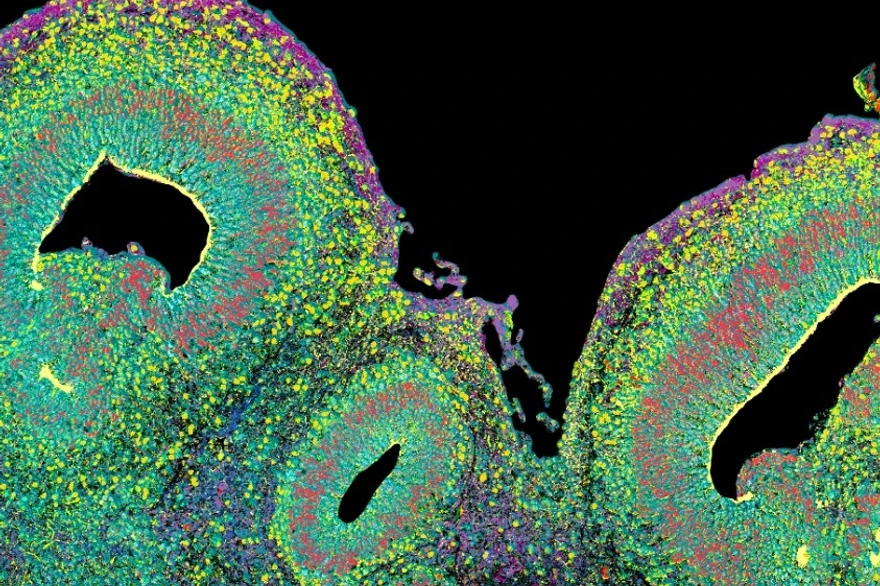

Machine learning is transforming the study of human health, offering deep insights into individual cell behavior. Building on existing knowledge that biases in machine learning can impact fairness and accuracy, a new study, led by Theresa Willem, AI Ethics Consultant at Helmholtz AI, and Prof Fabian Theis, Head of the Computational Health Center at Helmholtz Munich, specifically assesses critical biases in models designed for human single-cell data. Their findings highlight the need for careful evaluation to ensure reliable and equitable outcomes in healthcare and research.

The study analyzed biases in machine learning models trained on human single-cell data, tracing their origins and interactions across the development pipeline. This pipeline-informed approach highlights how biases interconnect, potentially amplifying their impacts and complicating mitigation efforts.